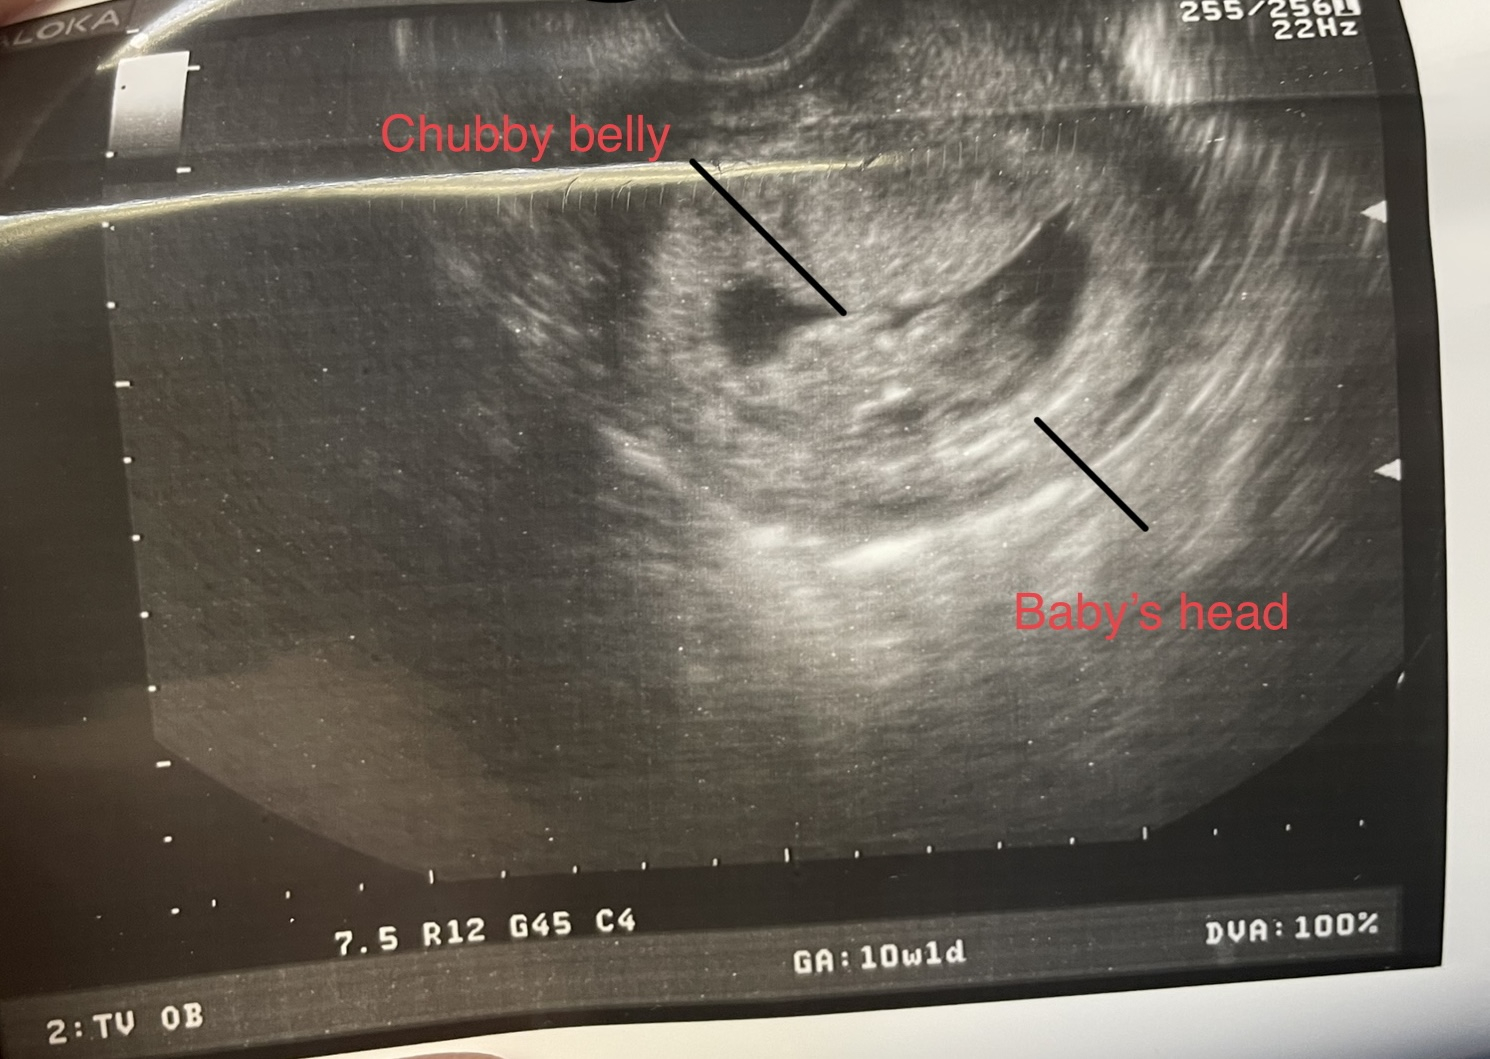

Finally got my ultrasound today! My EDD changed from 8/6 to 8/1 (but I love the crew in the august discussions board, it tried to get me to the July board but I’m sticking here)

Baby is 10w6d today! I’m a week ahead and a week closer from getting away from this damn morning sickness!!

Little peanut’s heartbeat is 165. I edited the photo to describe it. Look at that chunky belly!! And yes I cried too! My partner looked like a deer in headlights happy.